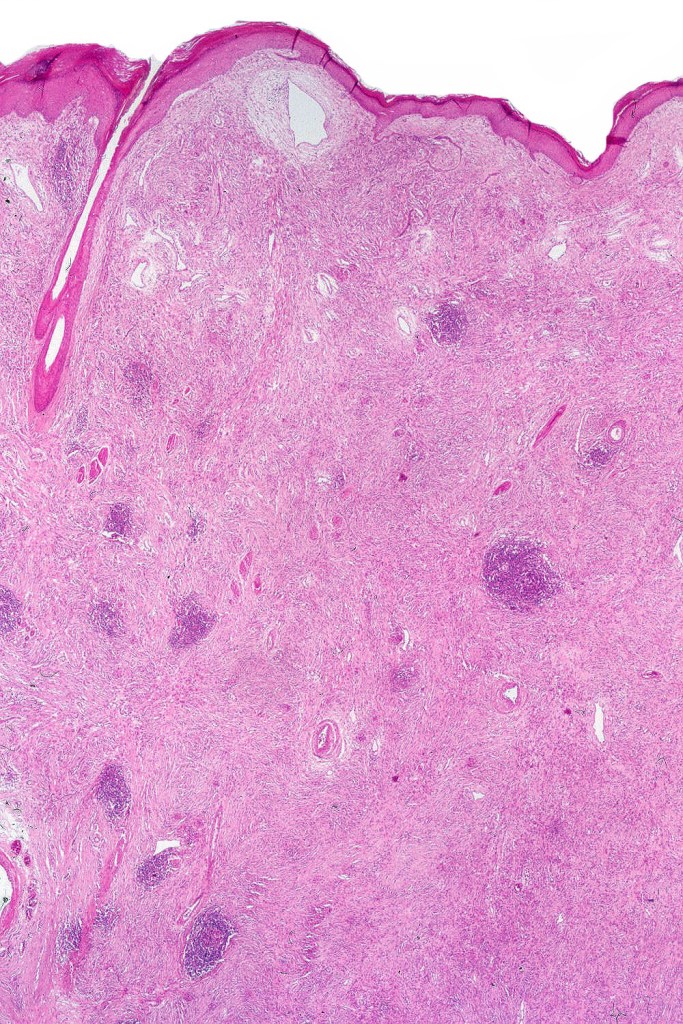

•Most characteristic is the dumbbell silhouette although a plague morphology may also be encountered

•Combined nevus variant

•An alveolar pattern is characteristic particularly with clear cell nodules

•Stromal fibrosis, myxoid change, vascular hyalinization with cyst formation are often seen

•Some tumors are composed spindle cells in a fascicular or neuronevoid pattern